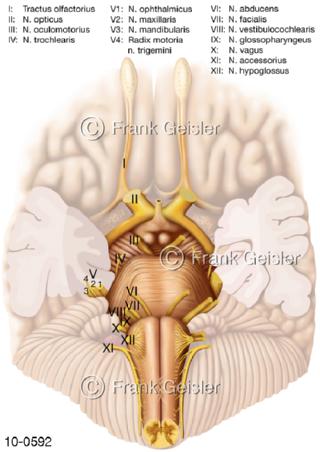

Bildergalerie Nervensystem

Bilder zum Nervensystem,dem Gehirn, Teil des zentralen Nervensystem, Zentralnervensystem ZNSmit Rückenmark, Abbildungen zum Nervengeflecht (Nervenplexus), die Verflechtungen von Nervenfasern, aus der Wirbelsäule hervortretende Nervenäst sowie Nervenzellen der Nerven